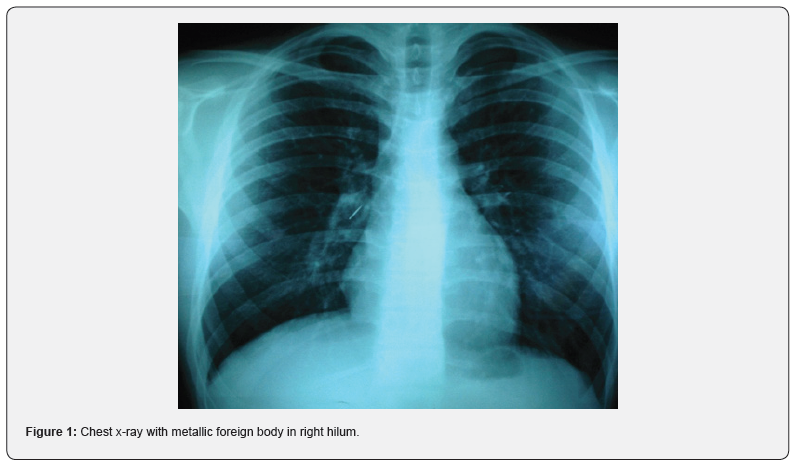

A 17-year-old male with no significant medical history presented to the emergency department with a complaint of a foreign body aspiration. He was playing with a thumbtack in his mouth when he sneezed. With the quick inhalation prior to the sneeze, the aspiration of the foreign body occurred. The patient only reported some cough and all vital signs were stable. A chest x-ray was performed which revealed the presence of a metallic foreign body in the right hilum (Figure 1). An urgent videobronchoscopy was performed that confirmed the presence of a metallic foreign body compatible with a thumbtack lodged at the entrance of the lower right lobe (Figure 2). The foreign body was extracted on the third attempt with a grasping forceps, revealing a 2.5 cm metallic-plastic thumbtack (Figure 3). Distal bronchial patency was confirmed after the extraction. The patient was discharged the same day without any complications during follow-up.